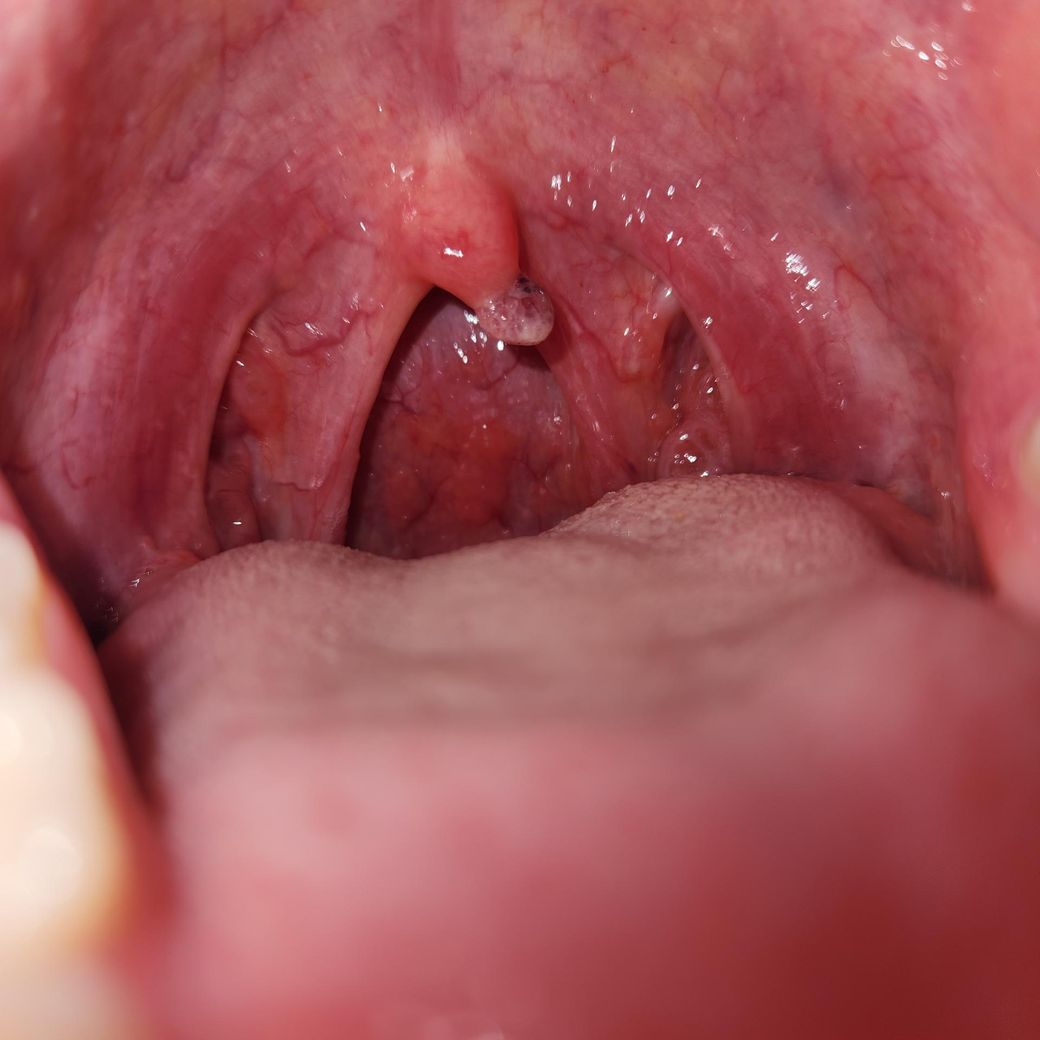

이게...뭐예요? 목젖에 거뭇거뭇한게 혹이났음

이거를 뭐 치료를 해여하는지...잘라내야하는지 병우ㅗㄴ가야하는지 이게 낫기는 하는건지 병명은 뭔지 재발 가능성은 있는지ㅠㅠㅠ

• 1번 째 사진

• 사진상으로는 목젖에 생긴 양성 병변이 가장 의심됩니다. 형태와 색을 보면 [ 구개수 유두종(편평사마귀 계열), 염증성 림프조직 증식, 또는 작은 혈관성 병변 ] 가능성이 큽니다. 급성 감염이나 암을 강하게 시사하는 소견은 아닙니다.

치료가 꼭 필요한 경우는 크기가 커지거나 이물감, 통증, 출혈, 반복적으로 부딪혀 불편할 때입니다. 이런 경우 이비인후과에서 국소마취 후 간단히 제거합니다. 제거 자체는 짧은 시술이며 회복도 빠른 편입니다. 증상이 거의 없고 크기 변화가 없으면 경과관찰만 하는 경우도 많습니다.

자연적으로 완전히 사라지는 경우는 드물지만, 대부분 양성이라 위험하지는 않습니다. 재발 가능성은 낮은 편이나, 유두종 계열이면 드물게 다시 생길 수는 있습니다.

정확한 병명 구분과 치료 여부 판단을 위해서는 이비인후과 진료를 권합니다. 사진만으로 확정 진단은 어렵습니다.